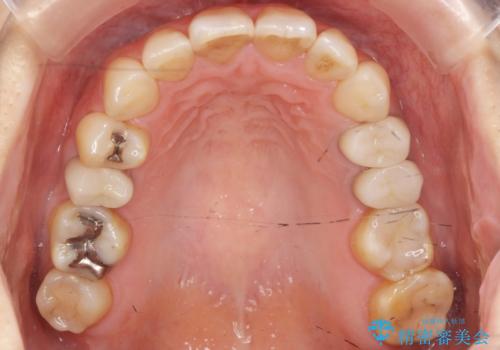

- 前歯の歯並びが気になることを主訴に来院された患者様です。

顎が小さく歯を並べるためのスペースが足りないため、

上下の前歯の歯と歯の間をすく処置(ディスキング)を行いました。

矯正後、右上5左上45セラミッククラウン・右下65左下5セラミックインレーによる補綴治療を行いました。

なお、左下の奥歯(左下7)は状態が悪く保存不可能と判断し矯正前に抜歯しております。